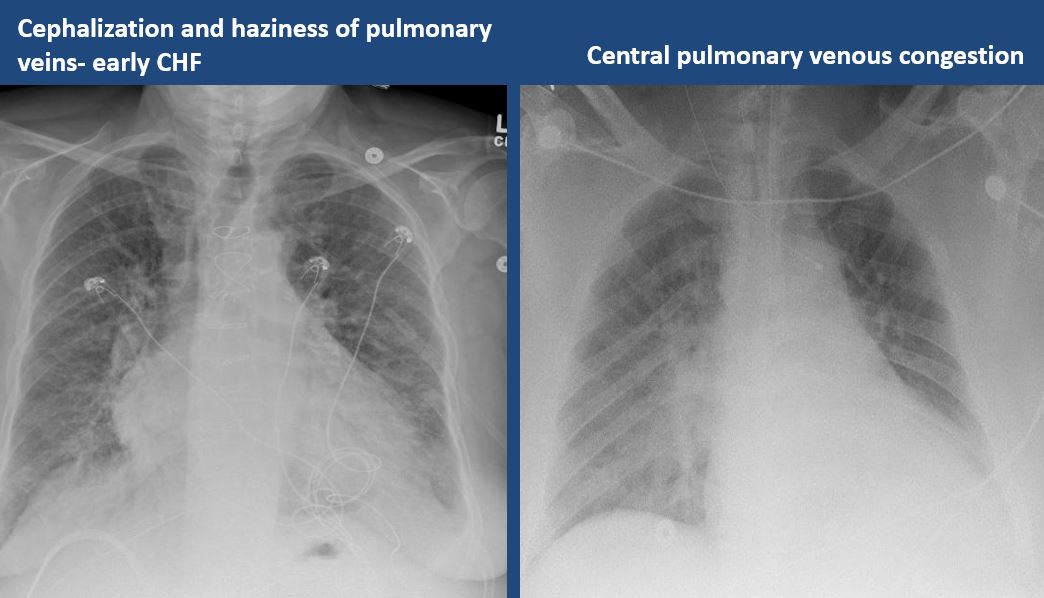

|

Yes | NA |

There is focal or diffuse interstitial disease. |